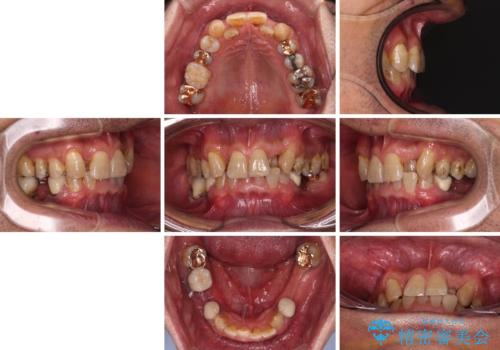

- 下顎両側の欠損と上顎前歯のデコボコを気にして来院された患者様です。

デコボコは今まで気にせずにいたそうですが、奥歯の欠損改善を機に、矯正治療に興味があるので、相談したいとのことでした。

奥歯に欠損が多く、矯正治療はやや難航することが予想されますが、患者様の希望もあり、上顎左右小臼歯を1本ずつ抜歯し、ワイヤー装置にて矯正治療を行うこととしました。

矯正歯科治療を行うに当たり、痛みや違和感を感じている歯の根管治療を行い、矯正治療中にインプラント埋入し、補綴治療と矯正治療を同時に終了できるように進めて行くこととしました。

銀歯やむし歯治療されている歯を抜歯する治療計画としたため、やや時間はかかりましたが、治療後の仕上がりには大変満足していただけました。